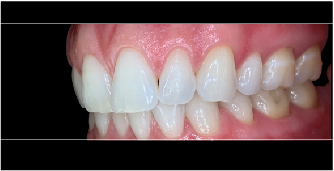

Fig 11. Esthetic treatment planning for a patient presenting for veneers is aided by the use of the SDL for photos taken by a dental assistant.

Figure 11